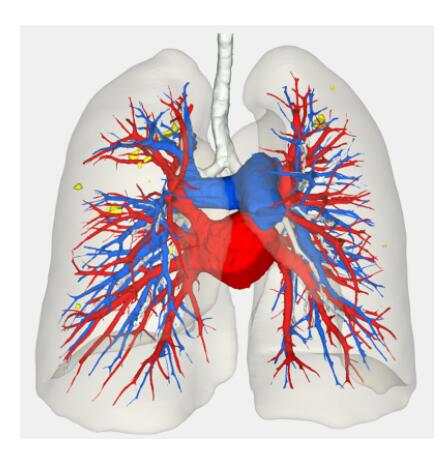

Segmentation

Segmentation of tissue (e.g., isolating the brain, differentiating gray and white matter) is performed using region-growing methods, filter operations as well as the application of 3D templates. Using the mouse it is very easy to explore a 3D volume with superimposed pseudocolor-coded statistical maps in a four-window representation showing a sagittal, coronal, transversal and oblique section. Based on a (segmented) 3D data set a three-dimensional reconstruction of the subjects' head and brain can be calculated and displayed from any specified viewpoint using volume or surface rendering.

Volume Rendering

Volume rendering is performed with a very fast ray casting algorithm; lightning calculations are based on Phong-shading. Surface rendering of reconstructed surfaces is performed using OpenGL. Using texture mapping, a reconstructed surface (e.g., head or brain) may be sliced in real time, showing both surface and volume data at the same time. Initial polygon meshes serve as the basis for surface finding, cortex inflation and cortex flattening computations.